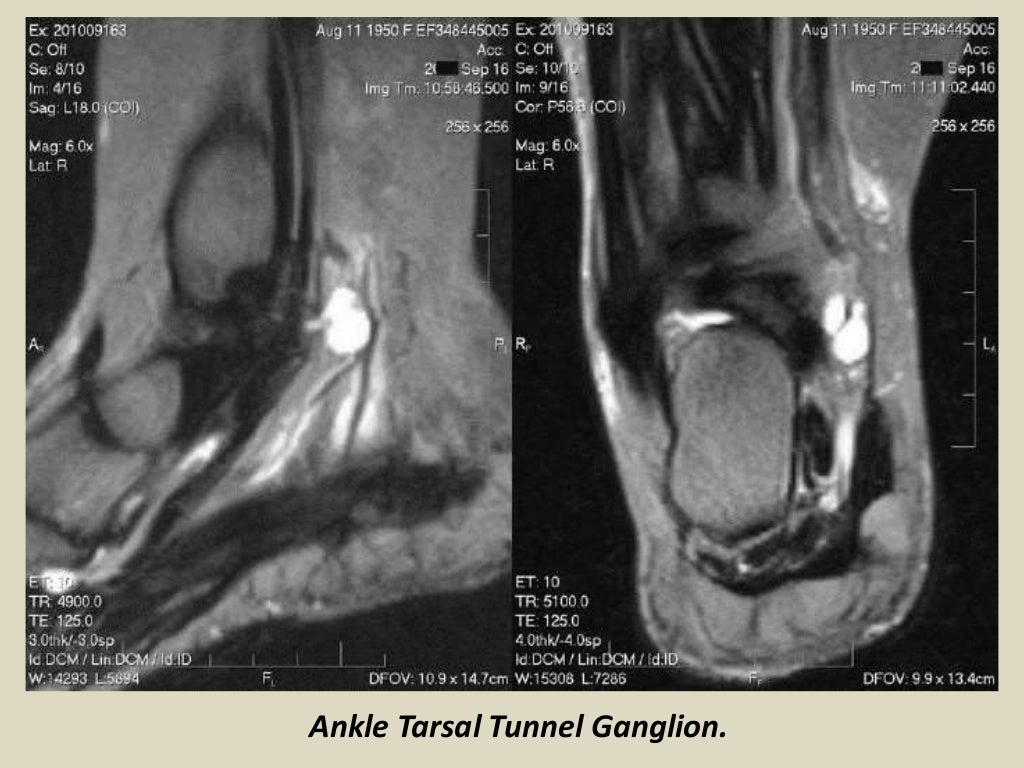

Presentation1 radiological imaging of tarsal tunnel syndrome.

Presentation1 radiological imaging of tarsal tunnel syndrome. Tarsal Tunnel Syndrome X Ray Tarsal tunnel syndrome refers to an entrapment neuropathy (tunnel syndrome) of the (posterior) tibial nerve or of its branches within the tarsal tunnel. Tarsal tunnel syndrome refers to an entrapment neuropathy (tunnel syndrome) of the (posterior) tibial nerve or of its branches within. Mr imaging can accurately depict the contents of the tarsal tunnel and the courses of the terminal. Tarsal Tunnel Syndrome X Ray.

Presentation1 radiological imaging of tarsal tunnel syndrome. Tarsal Tunnel Syndrome X Ray This condition is analogous to carpal tunnel. Tarsal tunnel syndrome is a compressive neuropathy of the tibial nerve at the level of the tarsal tunnel which can lead to pain. Tarsal tunnel syndrome (tts) is a common entrapment syndrome whose diagnosis can be difficult. Tarsal tunnel syndrome refers to an entrapment neuropathy (tunnel syndrome) of the (posterior) tibial nerve or. Tarsal Tunnel Syndrome X Ray.

Presentation1 radiological imaging of tarsal tunnel syndrome. Tarsal Tunnel Syndrome X Ray This condition is analogous to carpal tunnel. Tarsal tunnel syndrome is a compressive neuropathy of the tibial nerve at the level of the tarsal tunnel which can lead to pain. Tarsal tunnel syndrome refers to an entrapment neuropathy (tunnel syndrome) of the (posterior) tibial nerve or of its branches within the tarsal tunnel. Tarsal tunnel syndrome refers to an entrapment. Tarsal Tunnel Syndrome X Ray.